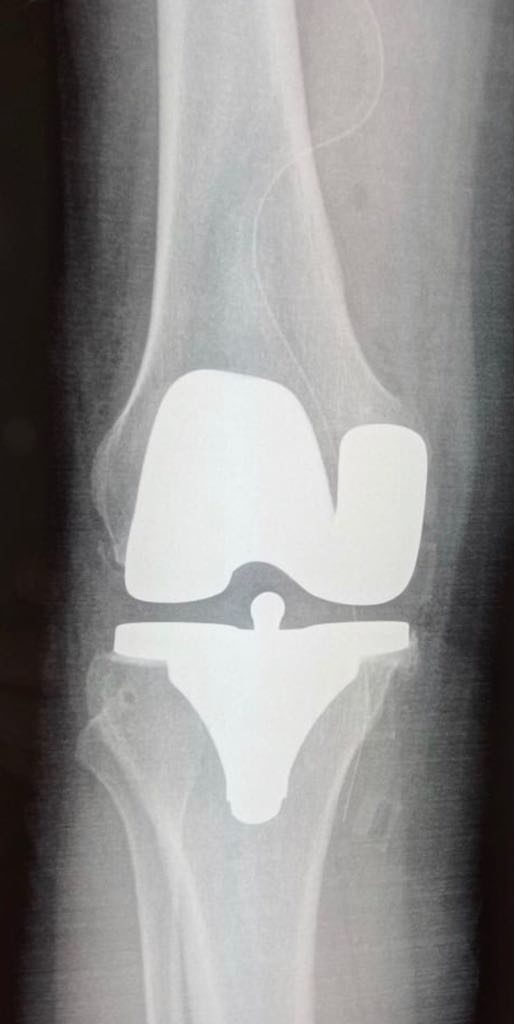

2- PTG postero-stabilisee cimentée

1- Gonarthrose sur Genu Varum